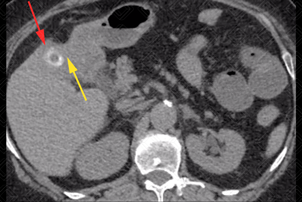

Texto alternativo para a imagem Figura 1. Créditos: Dra. Elazir Mota - Rio de Janeiro/RJ

Descrição das imagens: Tomografia computadorizada de abdome sem contraste. Vesícula biliar apresentando cálculo no seu interior (seta vermelha). Observe que não há um plano de clivagem nítido entre a vesícula biliar e o bordo duodenal (seta amarela), inclusive com uma duvidosa solução de continuidade entre eles. Na porção mais inferior do abdome, vemos distensão líquida gasosa, com caracterização de um ponto de transição de calibre no íleo distal por cálculo biliar (seta verde), confirmando a presença de íleo biliar.

Íleo biliar: C ausa rara de obstrução mecânica do intestino delgado e rara complicação de colecistite crônica. Este quadro ocorre quando há passagem do cálculo da vesícula biliar para o intestino delgado, por meio de fístula (fístula bilioentérica).

• Tomografia computadorizada do abdome: T rata-se d o exame de escolha diante desta suspeita por permitir boa caracterização do cálculo no interior da alça intestinal. Apresenta uma acurácia, sensibilidade e especificidade elevadas. A tríade de Rigler inclui três achados de imagem: aerobilia, obstrução do intestino delgado e cálculo de via biliar ectópico (figura 2);